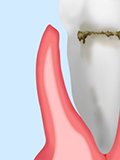

プラークが付着して歯ぐきが炎症を起こし、歯周ポケット(歯と歯ぐきの間の溝)が少し深くなっています。

まだ痛みはありませんが、ブラッシングすると出血することがあります。